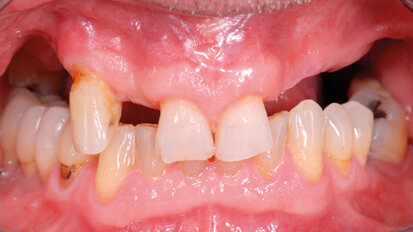

Mantenimento implantare:sondare o no?

I pazienti che si sono sottoposti a un intervento di implantologia necessitano di ricevere un follow-up continuo, sistematico e ...

salvare

I pazienti che si sono sottoposti a un intervento di implantologia necessitano di ricevere un follow-up continuo, sistematico e individualizzato. ...